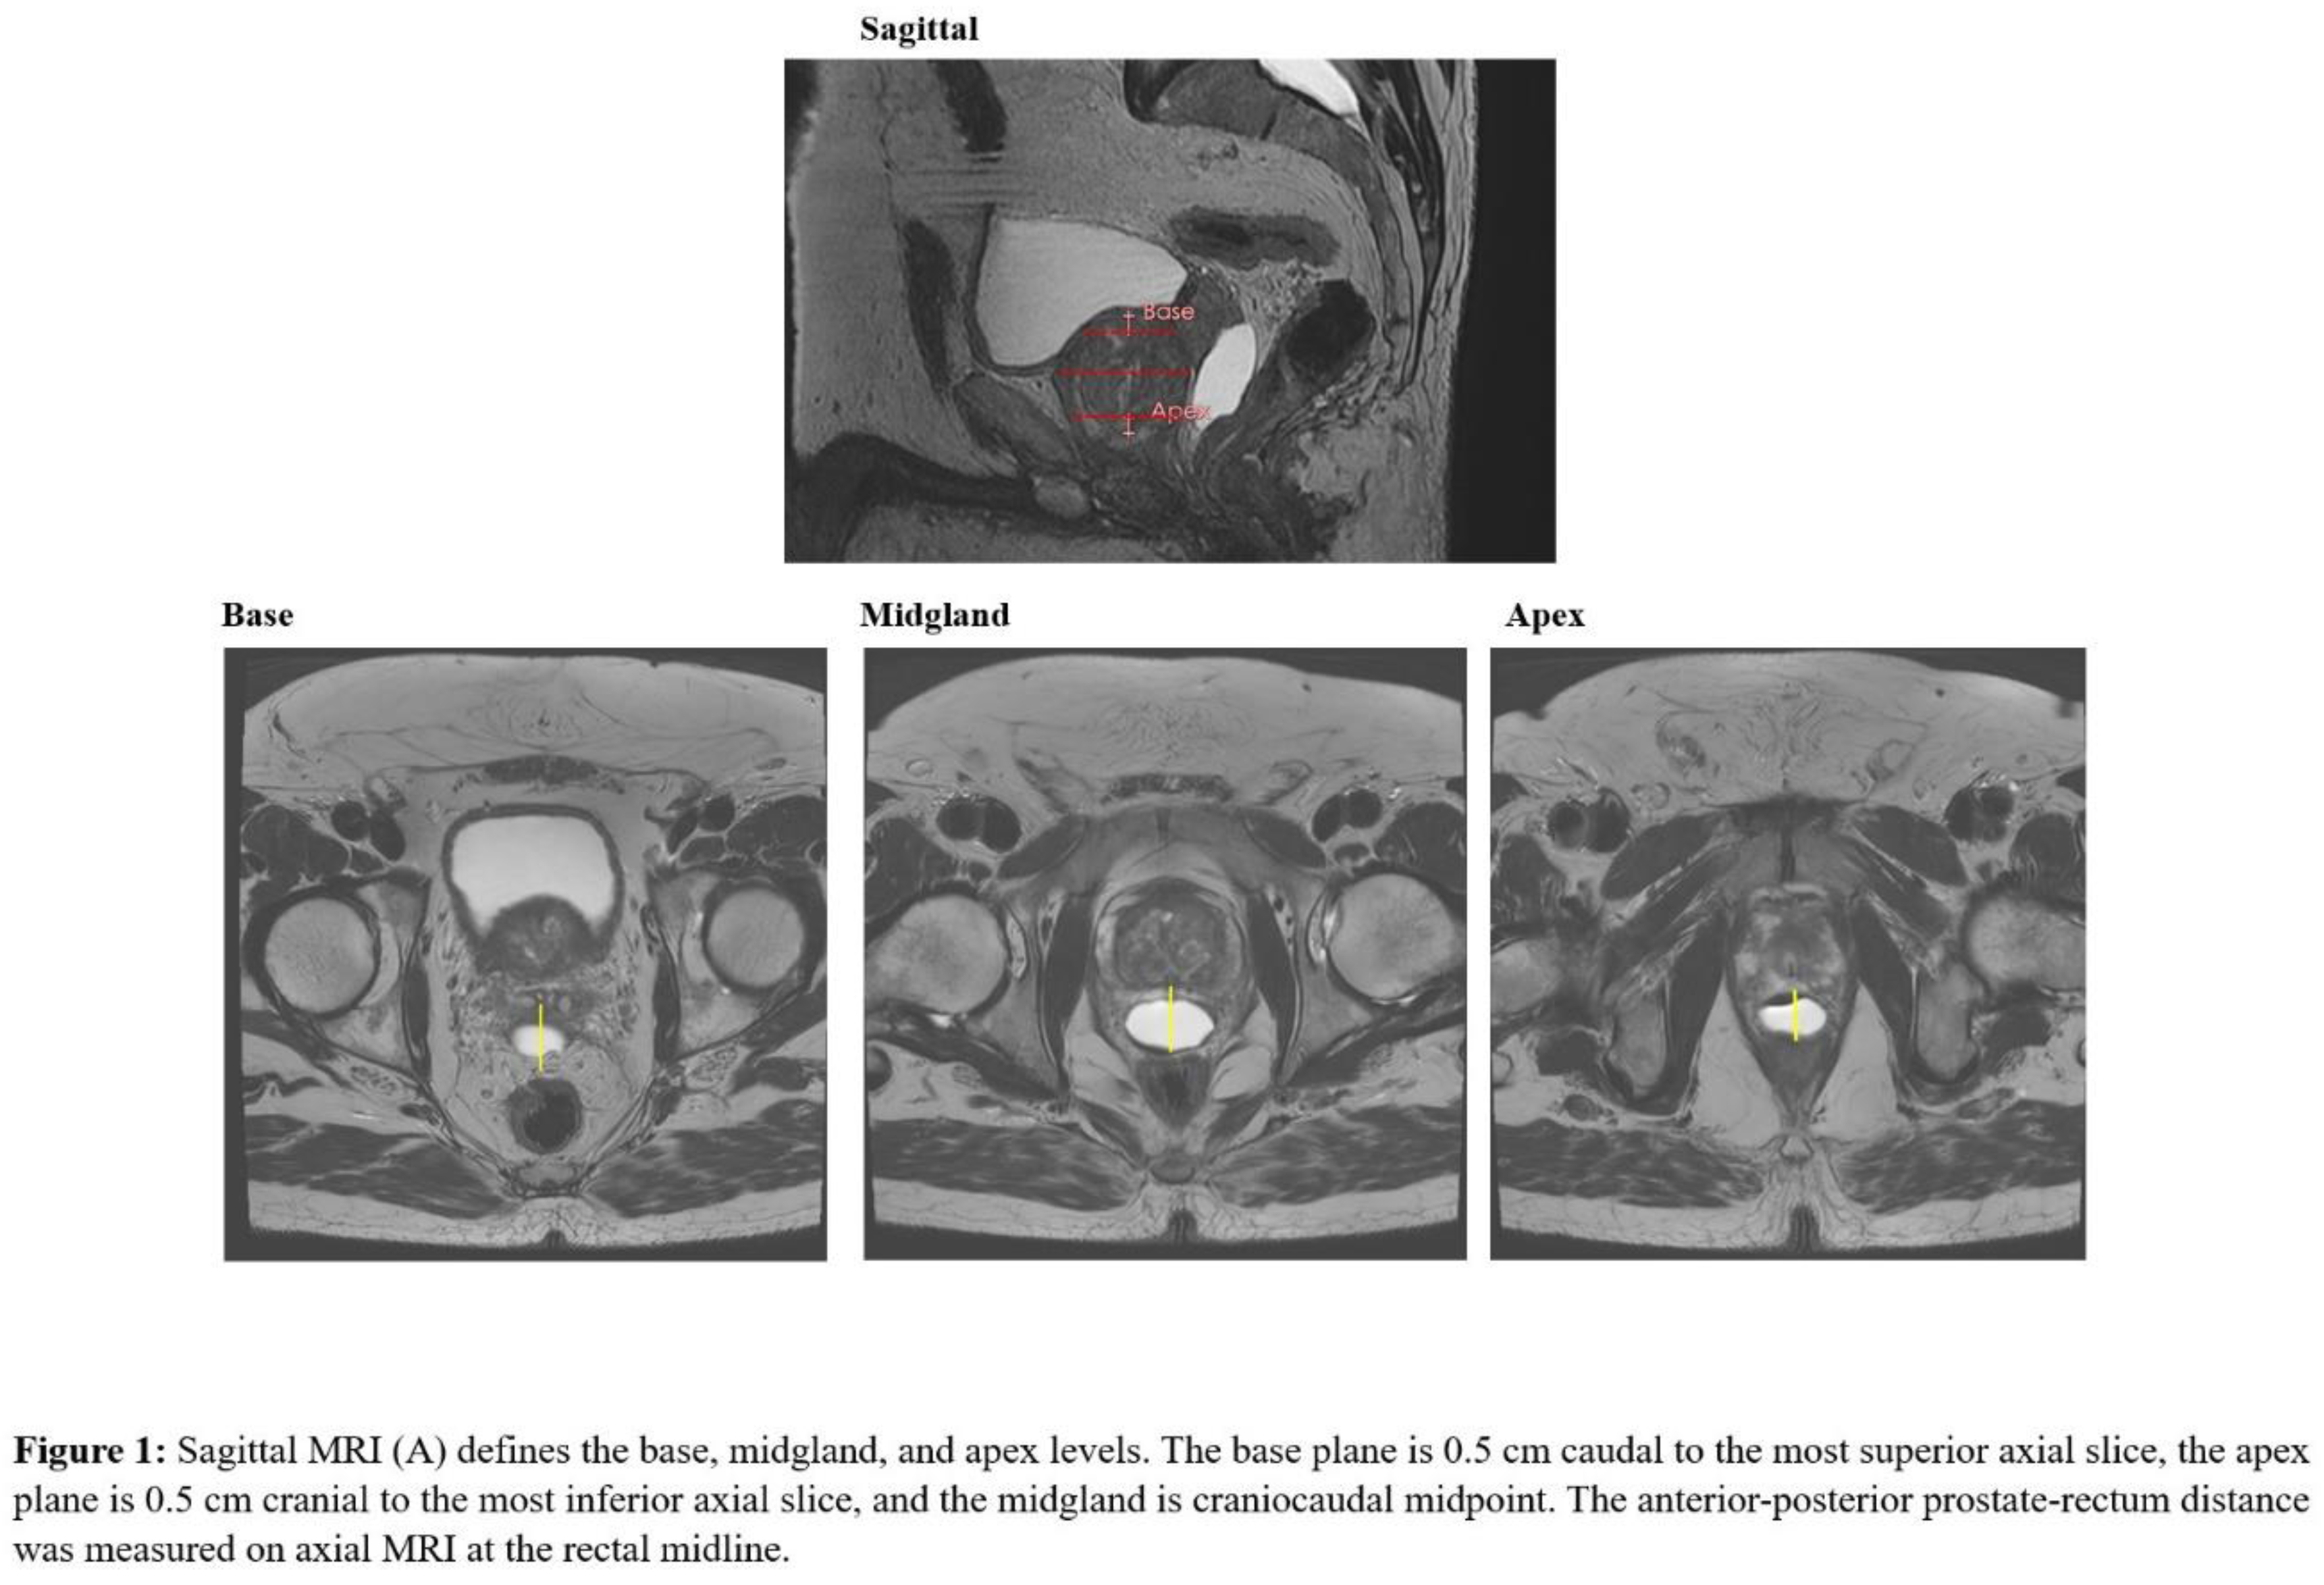

Prostate-rectum spacing was assessed in axial plane at mid-gland (center of the CTV), apex, and base. The mid-gland was defined as the central slice of the contoured prostate. To avoid partial-volume effects at the extremes of the gland, the apical plane was defined as 0.5 cm superior to the most caudal prostate slice and the base plane 0.5 cm inferior to the most cranial slice, as previously described (12). On each axial plane, spacing was measured at midline as the linear distance between the posterior prostate surface and the anterior rectal wall (Figure 1).

Figure 1.

Preprints 192872 g001